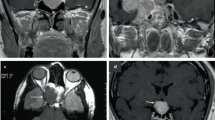

Frequent episodes of hypoglycemia were noted at the age of 3 months. He was diagnosed with central adrenal insufficiency based on low cortisol (2.2 μg/dl) and adrenocorticotropin (ACTH) (32 pg/ml) at a time of severe hypoglycemia (glucose 1.3 mmol/l). Further endocrine studies indicated that the patient also had central hypothyroidism on the basis of a low free T4 (0.50 ng/dl: Ref. 0.99–1.91) with an inadequately increased thyroid-stimulating hormone (TSH) level of 3.98 mU/l (Ref. 0.77–7.3), and growth hormone (GH) deficiency (Supplementary Table 1). The brain MRI exhibited anterior pituitary hypoplasia, visible but thin stalk, cerebellar hypoplasia and eutopic posterior pituitary. The olfactory bulb was difficult to identify. Replacement therapy with L-thyroxine, hydrocortisone and recombinant human GH was started at 3 months of age. At 13 years of age, he showed typical signs of hypogonadism, with small intrascrotal testes (1 ml), no pubic hair (Tanner stage 1) and a micropenis (stretched penile length 2.0 cm). Hormone assays revealed very-low plasma testosterone levels. The HH diagnosis was confirmed by LH-releasing hormone stimulating test (Supplementary Table 1).